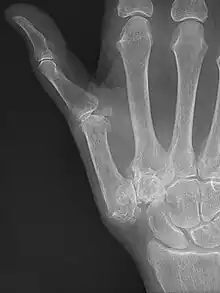

| Osteoarthritis of the trapeziometacarpal joint | |

Trapeziometacarpal osteoarthritis (TMC OA) is, also known as osteoarthritis at the base of the thumb, thumb carpometacarpal osteoarthritis, basilar (or basal) joint arthritis, or as rhizarthrosis.[3][1][2] This joint is formed by the trapezium bone of the wrist and the metacarpal bone of the thumb. This is one of the joints where most humans develop osteoarthritis with age.[4] Osteoarthritis is age-related loss of the smooth surface of the bone where it moves against another bone (cartilage of the joint).[3][5] In reaction to the loss of cartilage, the bones thicken at the joint surface, resulting in subchondral sclerosis. Also, bony outgrowths, called osteophytes (also known as “bone spurs”), are formed at the joint margins.[6]

TMC OA is diagnosed based on symptoms and signs.[8] Radiographs can confirm the diagnosis and the severity of TMC OA. Other diagnoses in this region include scaphotrapezial trapezoid arthritis and first dorsal compartment tendinopathy (De Quervain syndrome) although these are usually easy to distinguish.